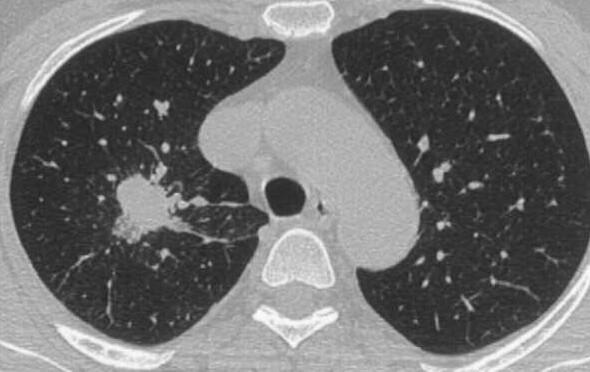

Here we report on a 60-year-old female patient with DIPNECH and an associated pulmonary adenocarcinoma.

在此,我们报告一名患有DIPNECH及相关肺腺癌的60岁女性患者。